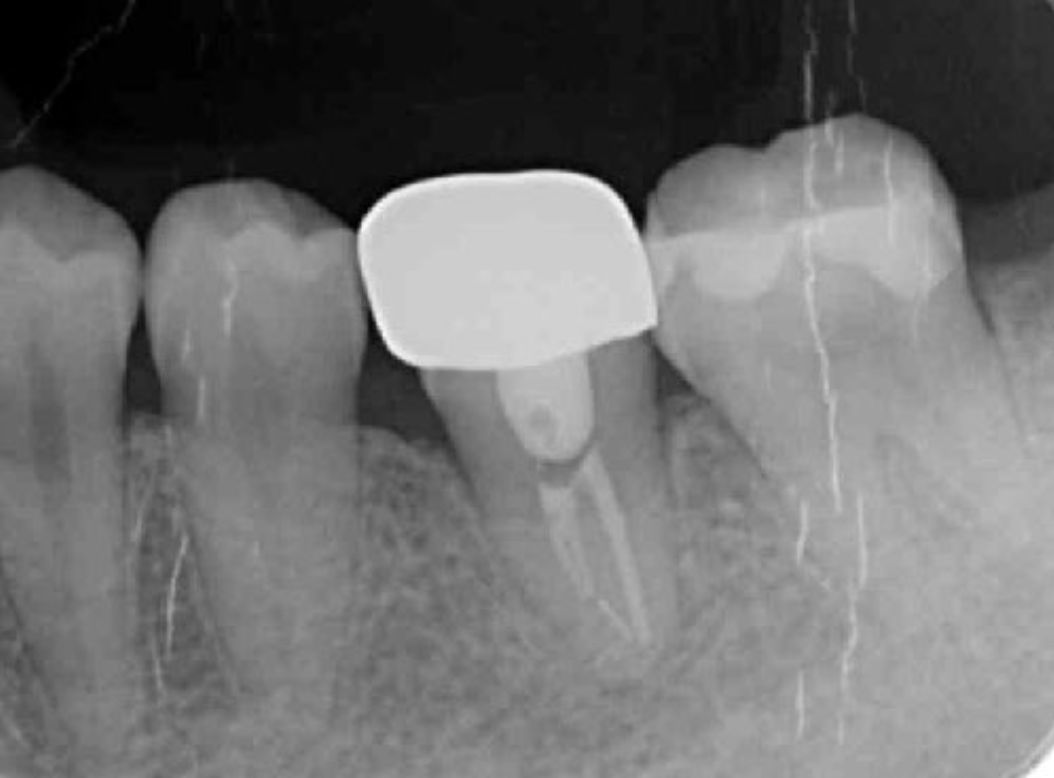

Figure 2.Pre-treatment X-ray findings. A cystic lesion was found in the mesial and distal roots apex, and root nodule of #46.

Following detailed examinations, the situation was explained to the patient and autotransplantation was suggested as preferred treatment. Since a single-rooted wisdom tooth (#48) with no periodontal pathology and a root morphology similar to that of #46 was present, it was determined to be an adequate donor tooth

To determine adaptability of the donor tooth to the recipient site, the dimensions of both were carefully measured using CBCT images. It was thus determined that the morphology of the tooth root was a single root and the risk of damage to the periodontal ligament during extraction was estimated to be low.

The transplantation process begins with a surgical procedure according to the following requirements; the recipient site should be prepared according to the donor tooth shape, time needed for recipient site preparation should be minimized, the number of fitting attempts using the donor tooth should be as few as possible, and extraction of the donor tooth should be gently performed. For realization of an ideal surgical setting, panoramic X-ray and CBCT results (Fig. 1-9) are essential for preoperative diagnosis. In the present case, root completeness, Moorrees classification 18, and donor tooth size were determined based on those results, which allowed us to form an operation plan. Regarding root morphology, a single rather than a compound root is ideal and a single-root tooth that tapers toward the root apex is best, as the risk of damage to the periodontal ligament during extraction is reduced.